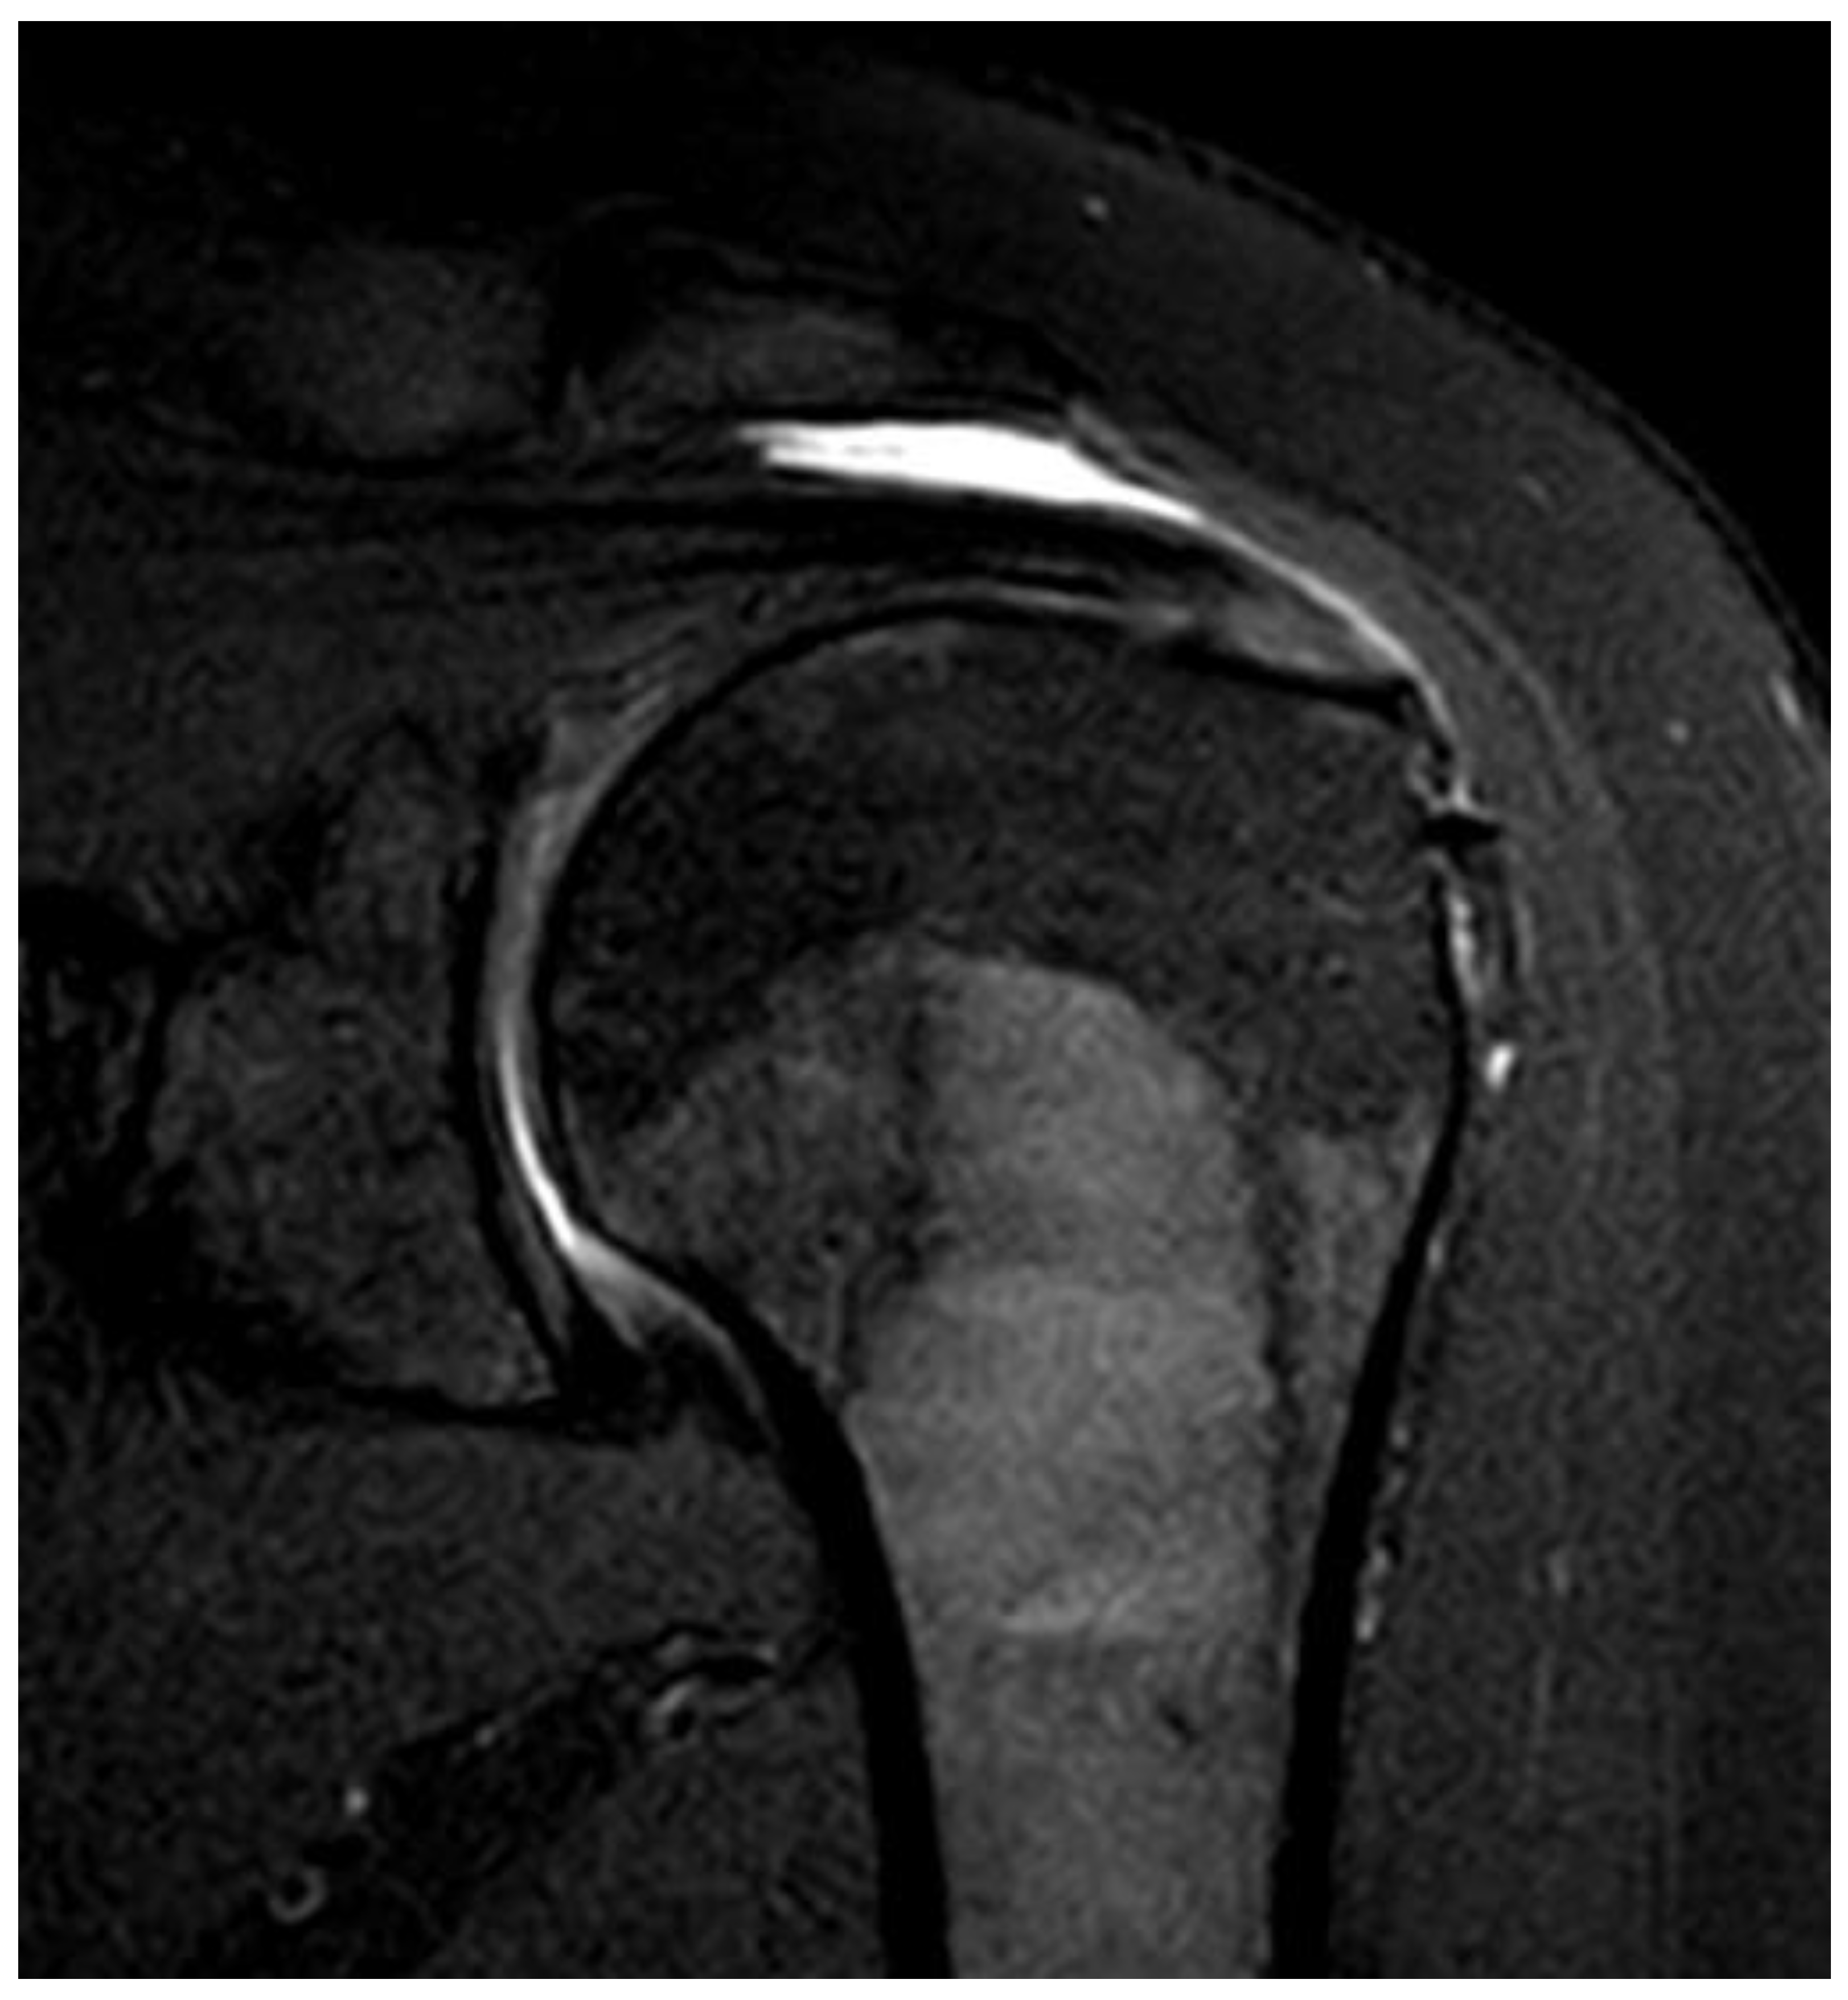

Figure 2. (A) Bursal side partial thickness supraspinatus tear with subacromial spur was observed on the preoperative magnetic resonance imaging. (B) Bio-inductive collagen implant located on the tendon is observed in a post-operative magnetic resonance image. (C) A magnetic resonance image 6 months after surgery showed that the bio-inductive collagen implant was absorbed and the bursal side partial tear was fully recovered.